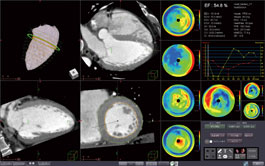

Utilizing multi-phase MR images of the heart, this protocol segments the inner and outer walls of the left ventricle, and calculates ejection fraction, wall thickness, wall thickness ratio and regional wall motion.

Utilizing multi-slice CT images of the heart, this protocol segments the inner and outer walls of the left ventricle, and calculates ejection fraction, wall thickness, wall thickness ratio and regional wall motion.